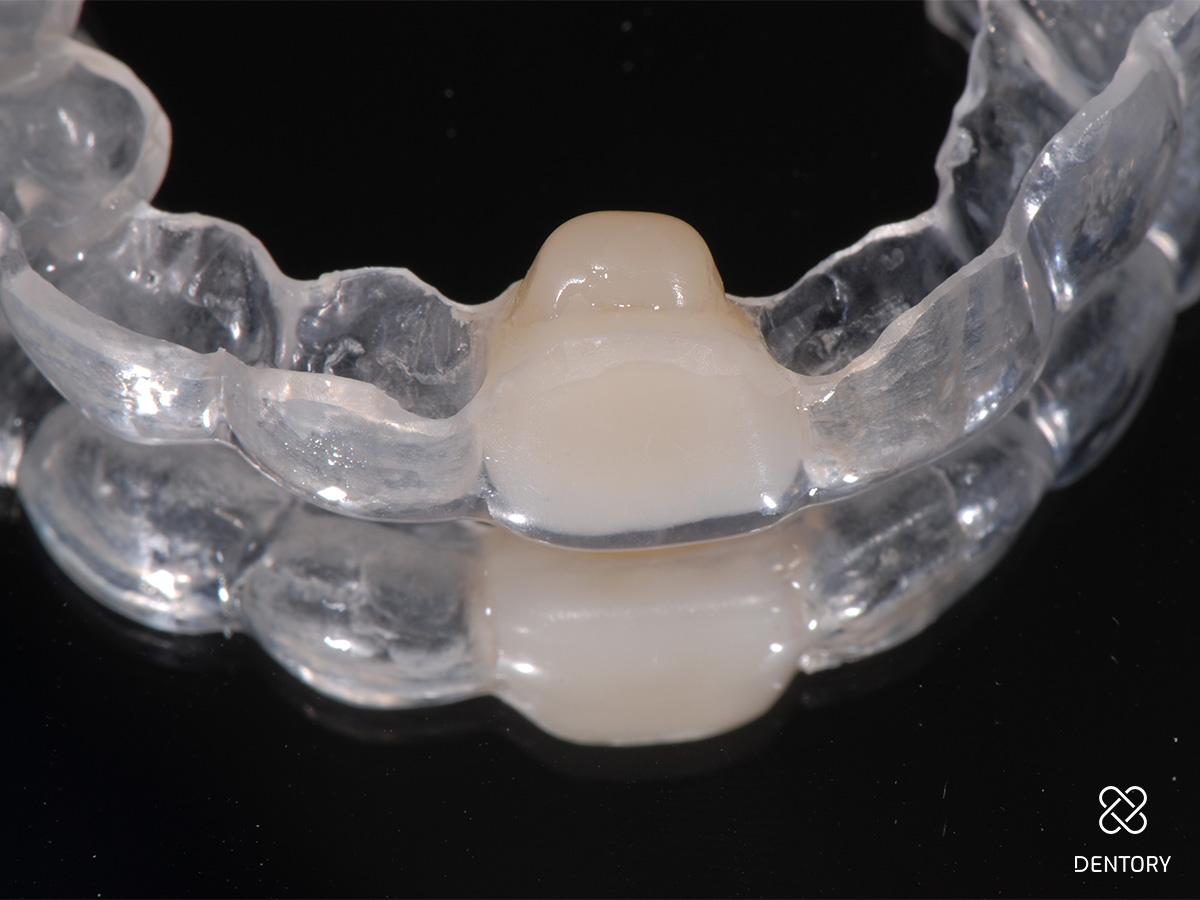

Abbildung 12

Provisorische Versorgung mit einer Tiefziehschiene; alternativ kann auch eine kleine Prothese oder eine Klebebrücke verwendet werden.